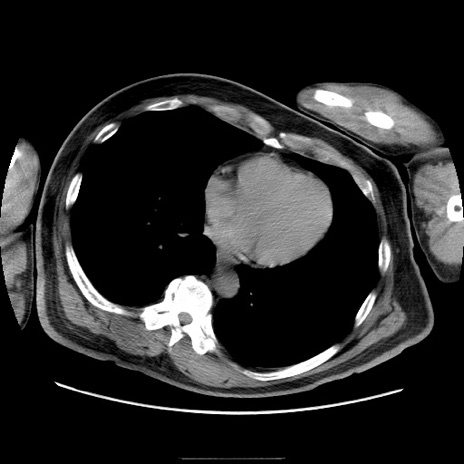

冠状断像

【症例】50歳代男性

【主訴】腹痛

【現病歴】AVMからの被殻出血のため回復期リハ病棟入院中。 本日午後3時頃急に下腹部痛が出現した。

【既往歴】AVM、被殻出血、虫垂炎、高血圧

【身体所見】意識晴明、左半身不全麻痺、会話の理解は良好、36.5°C、腹部:膨隆、全体に板状硬、下腹部正中に圧痛点あり、反跳痛-、筋性防御不明、右下腹部にope scar

【データ】WBC 9400、CRP 0.06